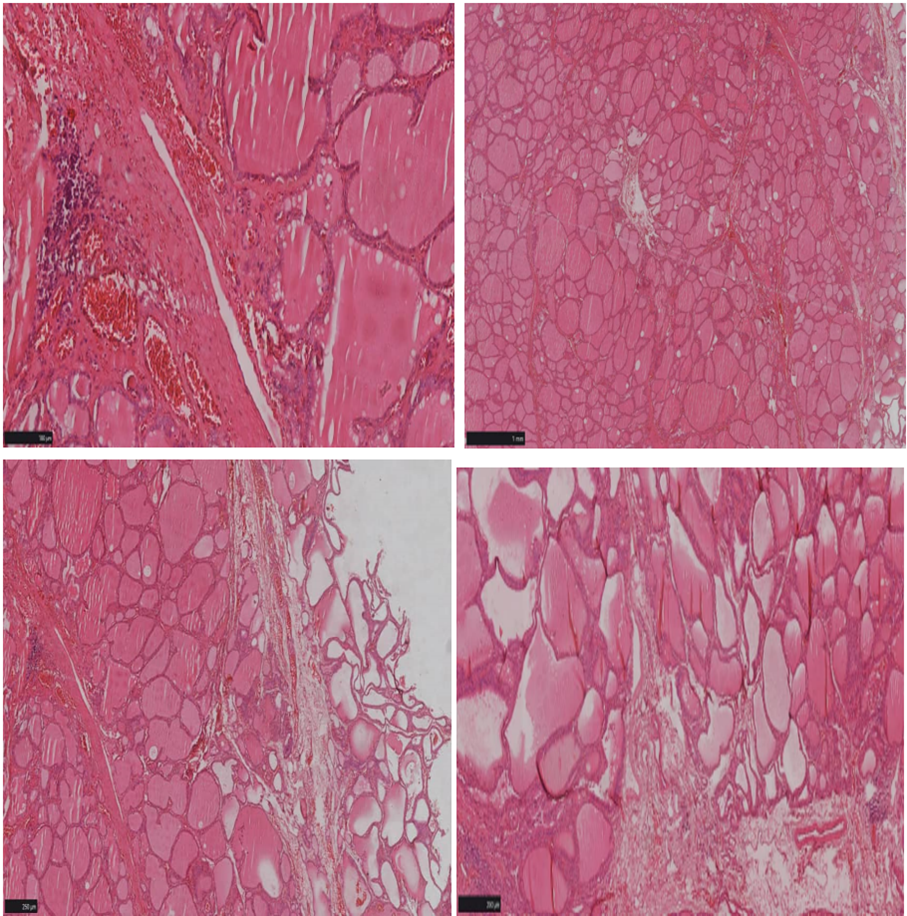

The histopathological examination of the thyroid biopsy specimens and thyroid nodules revealed the following (Figure 4). The thyroid tissue fragments showed follicles arranged in nodules, separated by connective tissue septa, without any atypical features. The follicular epithelium was regular and cuboidal. In addition, there were follicles lined with cuboidal epithelium exhibiting pseudo-papillary projections, along with fibrosis, congestion, and a lymphocytic inflammatory infiltrate, all without any signs of malignancy. The colloid was pale with resorption vacuoles at the periphery. In conclusion, this is a case of nodular goiter associated with Graves' disease, consistent with the Marine-Lenhart syndrome. He is regularly monitored by the General Surgery and Internal Medicine teams.

Figure 4: Histological examination of the thyroid gland.